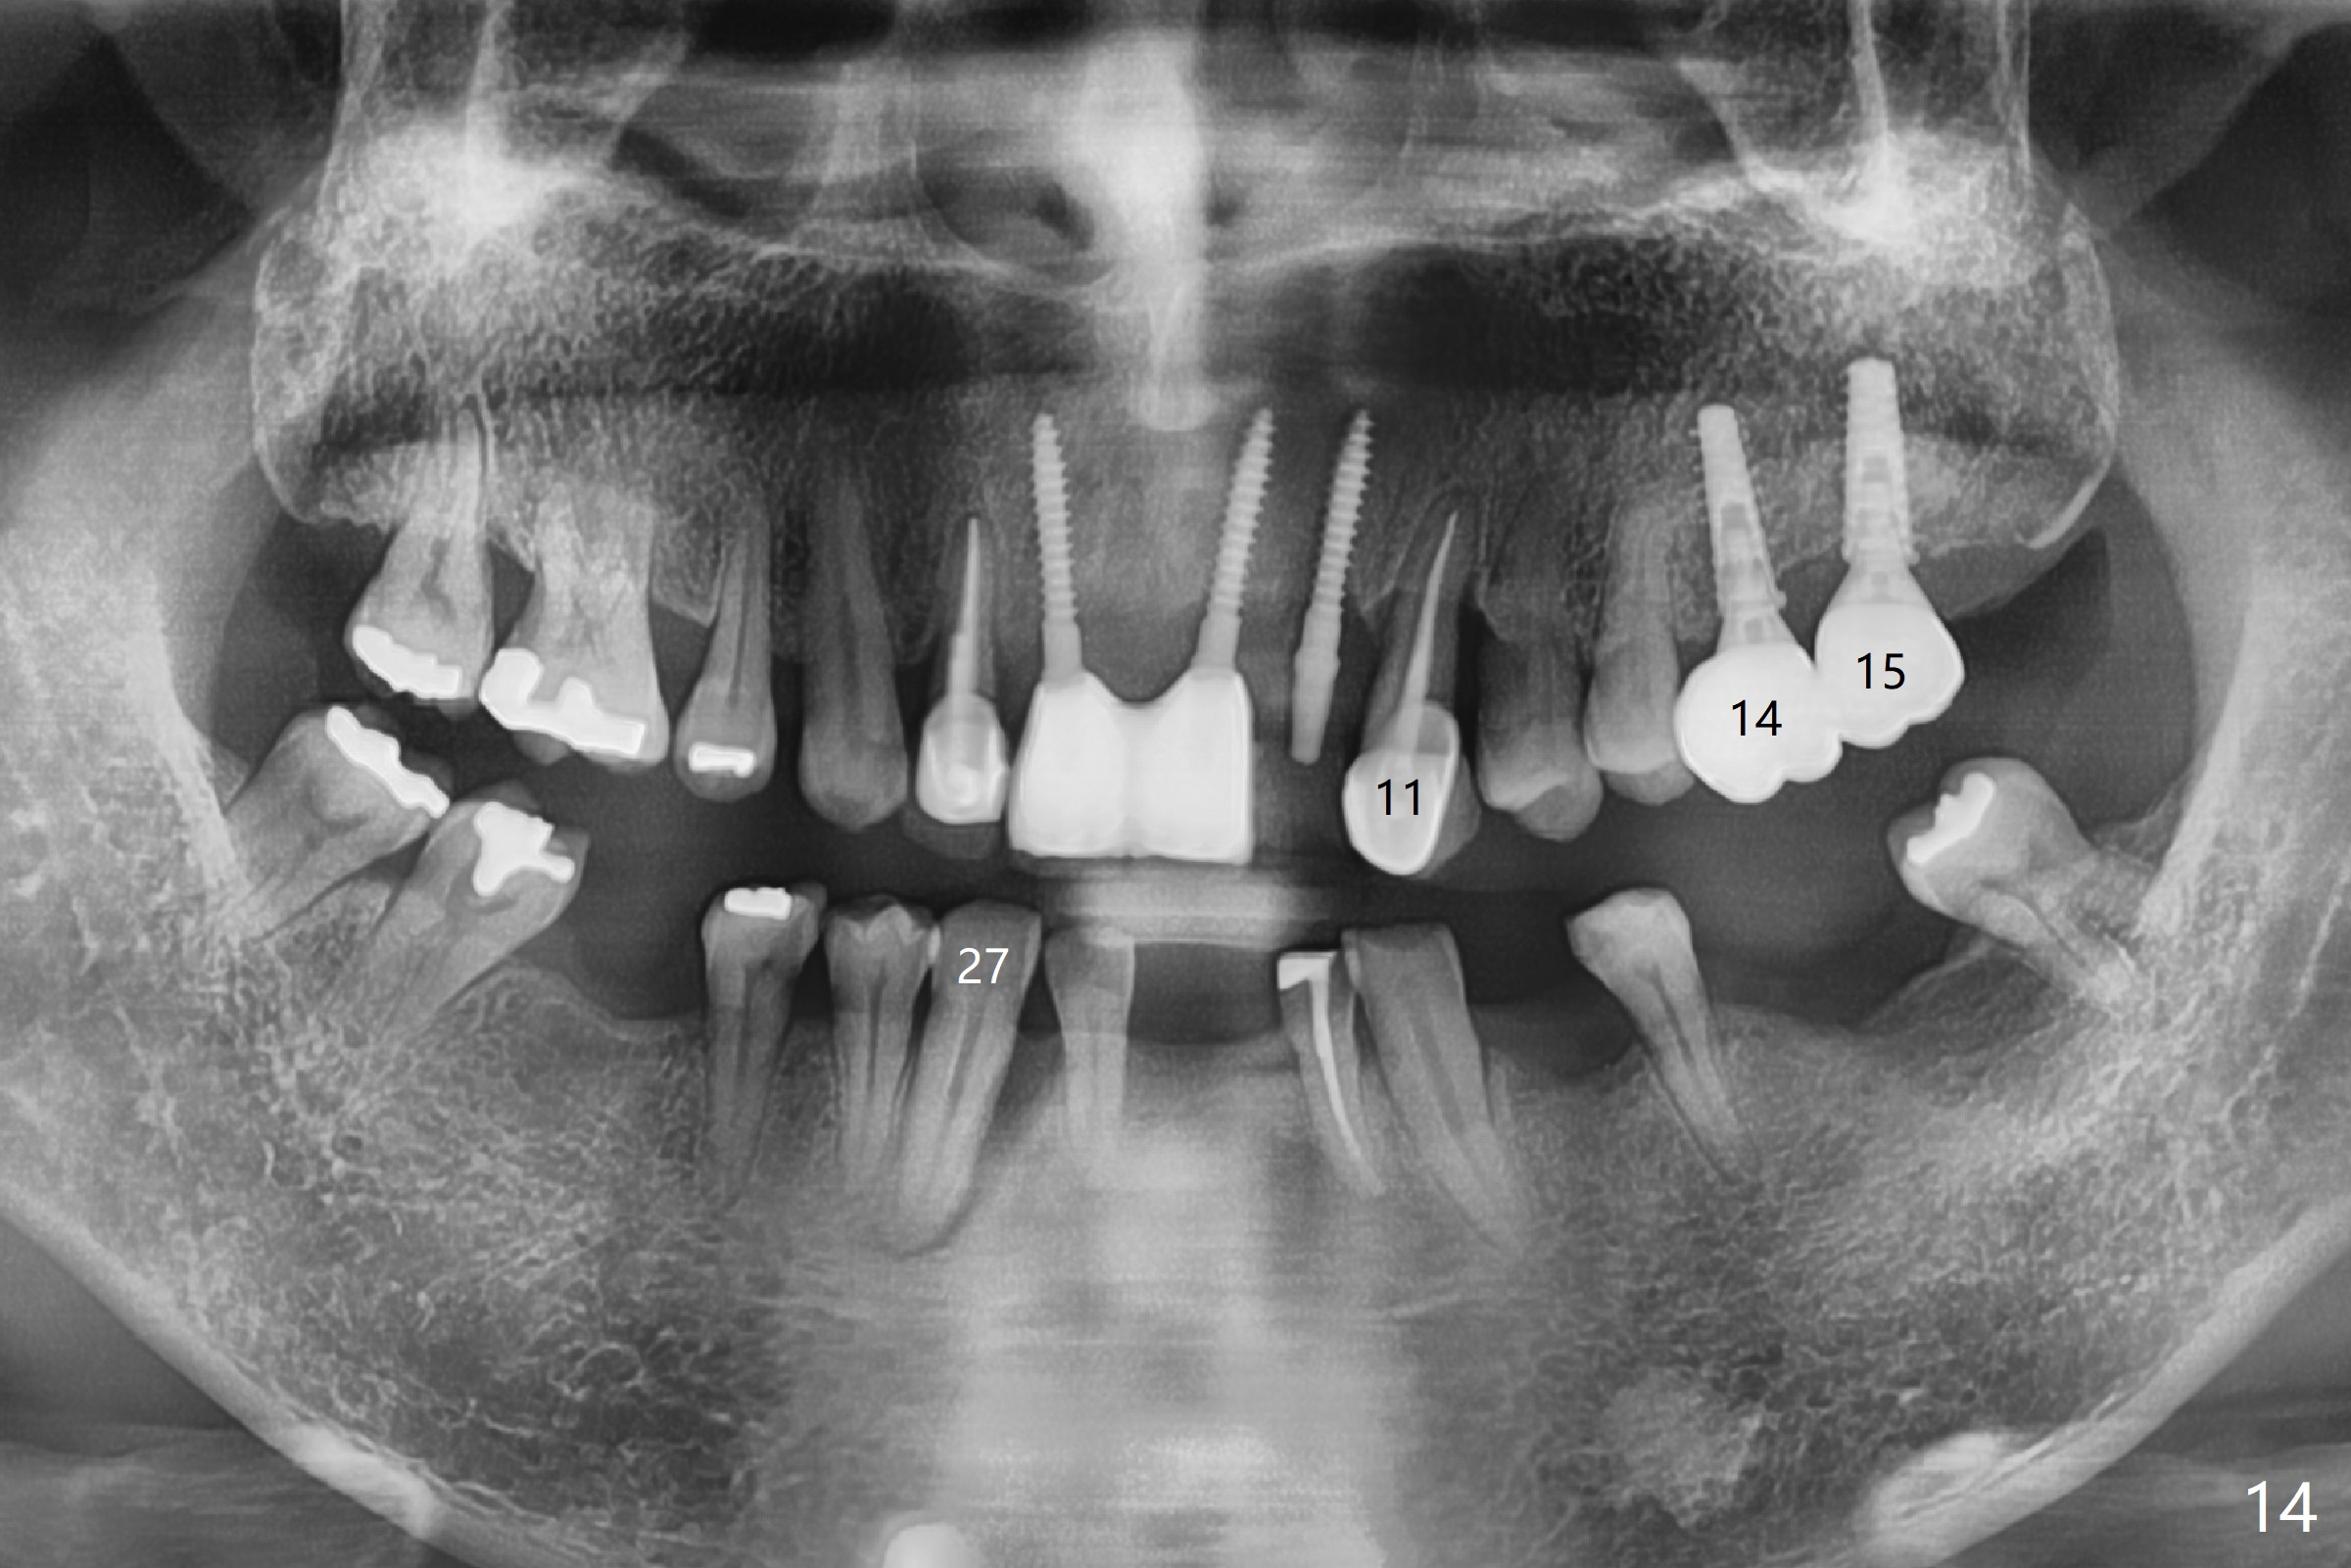

There is severe bone loss at #11 and 27. The implants at #14 and 15 were placed free hand (not parallel). Guided surgery should be done more often. Panoramic X-ray is taken 2 years 2 months post cementation.